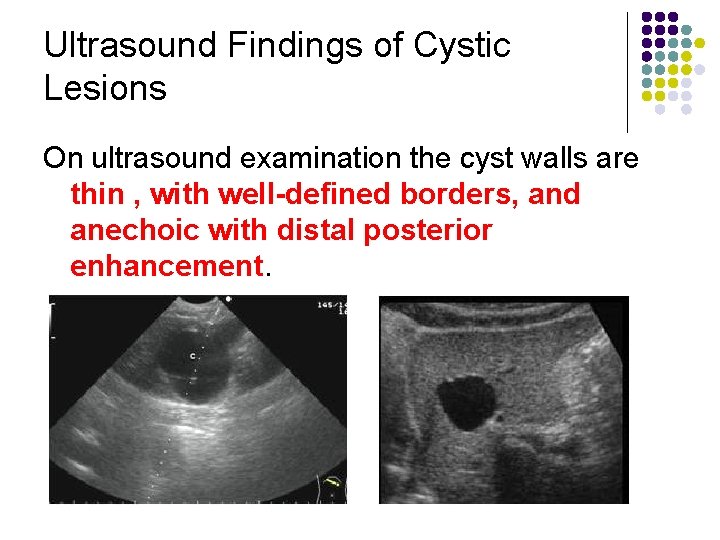

Ultrasound Findings of Cystic Lesions On ultrasound examination the cyst walls are thin , with well-defined borders, and anechoic with distal posterior enhancement.

Sonographic Features Of hepatic cyst: l No internal echoes l Smooth borders l Regular /irregular outline l Acoustic enhancement l Septum may be seen